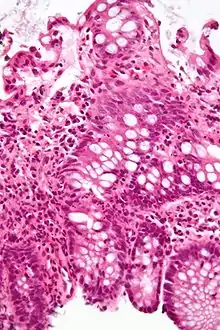

| A micrograph demonstrating cryptitis, a microscopic correlate of colitis. H&E stain. | |

An important investigation in the assessment of colitis is biopsy for histopathology. A very small piece of tissue (usually about 2mm) is removed from the bowel mucosa during endoscopy and examined under the microscope by a histopathologist. A biopsy report generally does not state the diagnosis, but should state any presence of chronic colitis, give an indication of disease activity, as well as state the presence of any epithelial damage (erosions and ulcerations).[4]

Histopathology findings generally associated with chronic colitis include:[4]

Crypt degeneration

Crypt branching and other architectural distortions

Paneth cell (pictured) or gastric metaplasia (only applies in the left colon and rectum)

Other findings include basal plasmacytosis and mucin depletion.[4] Histopathology findings generally associated with active colitis include:[4]

Neutrophilic cryptitis (neutrophils within crypt epithelium)

Crypt abscesses (luminal neutrophilic aggregates)

Gland destruction

Ulceration (seen here as absence of epithelium, and granulation tissue with many fibroblasts)